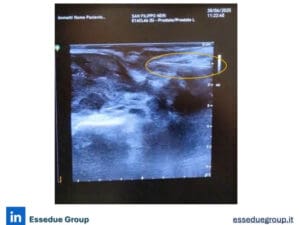

Si tratta di uno spaziatore sintetico assorbibile in idrogel, progettato per creare un cuscinetto temporaneo tra prostata e retto, riducendo così l’esposizione del retto alle radiazioni durante il trattamento.